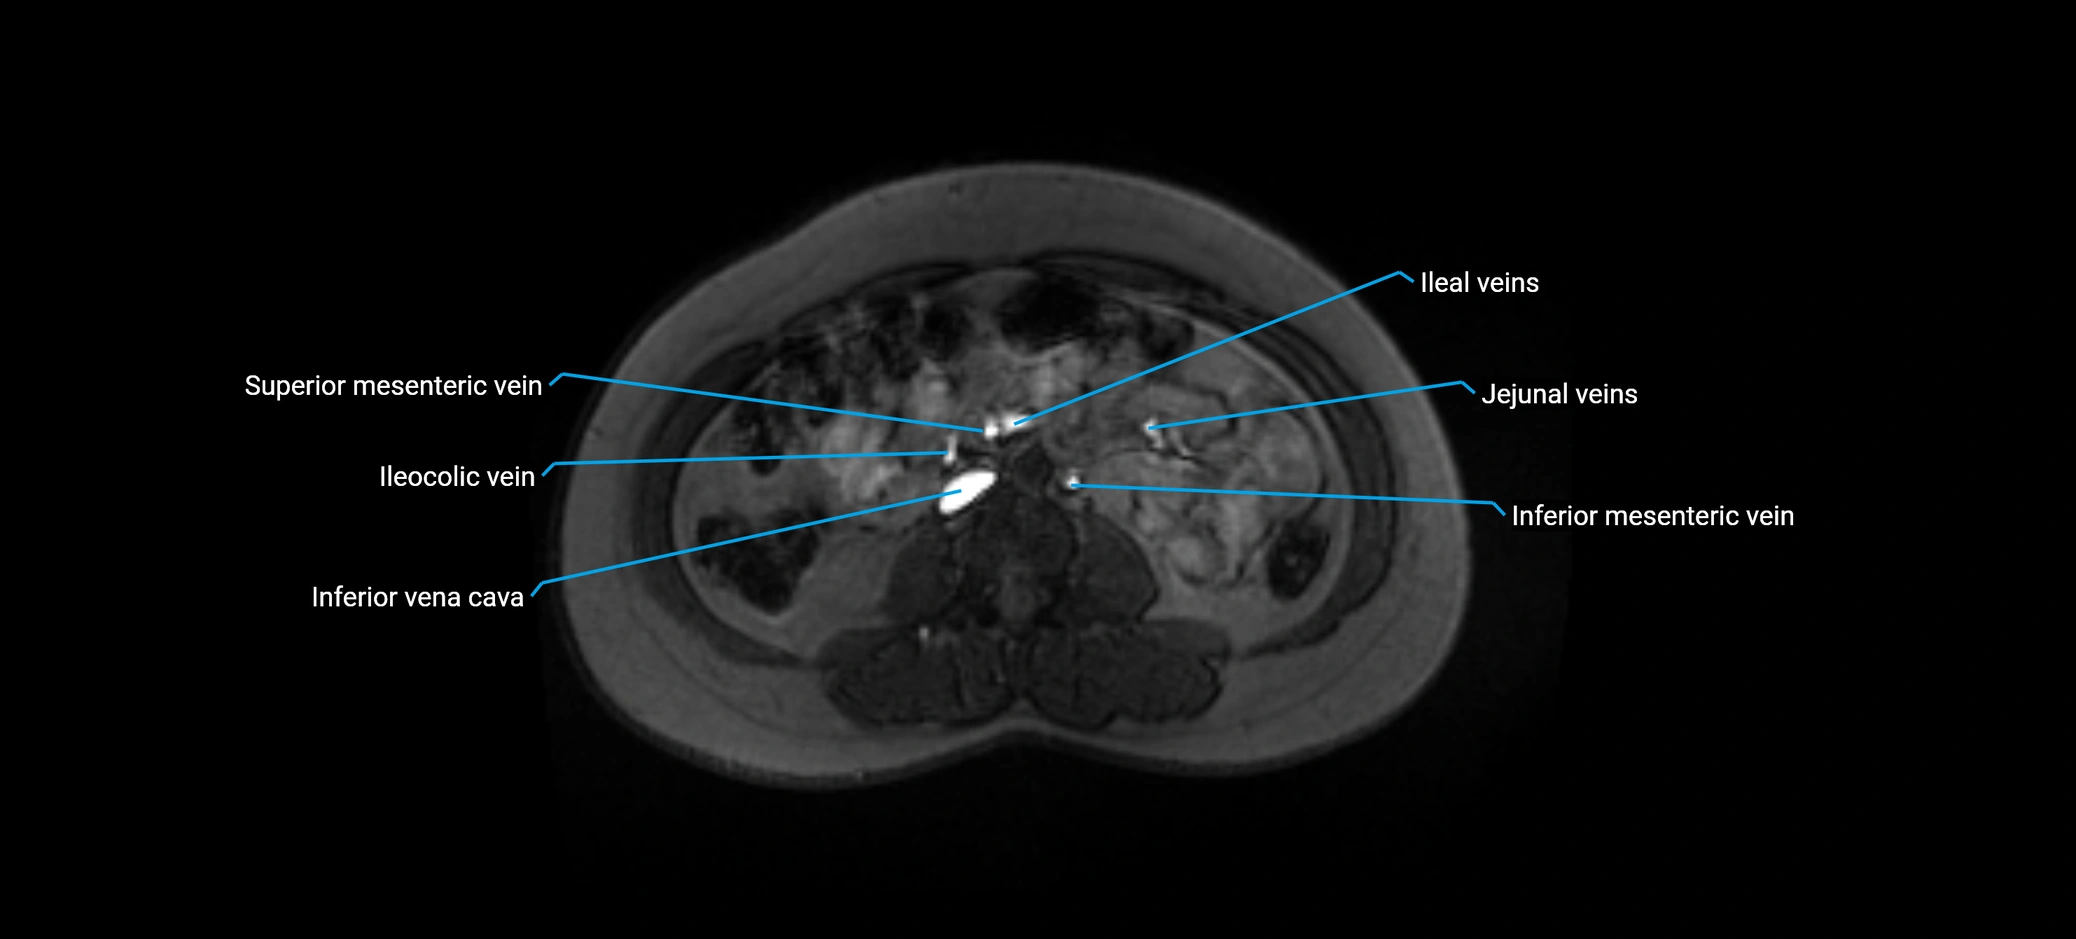

MRI image

image